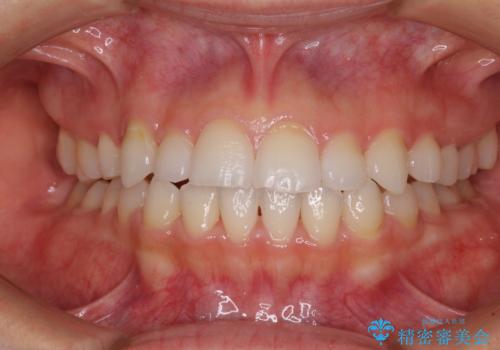

上下前歯が接触しない オープンバイトをインビザラインで改善

オープンバイト(開咬)を非抜歯インビザラインで治す